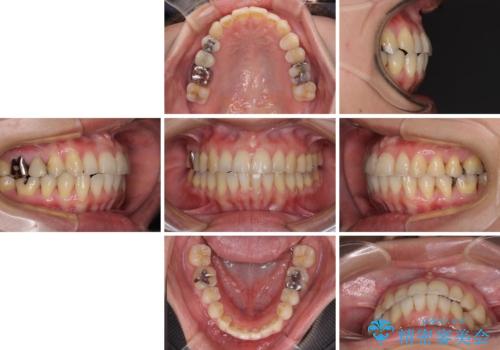

切端咬合をインビザライン矯正で解消

治療途中に前歯に歯髄充血を思わせる痛みが認められたため、無理のない歯の移動と頻繁な経過観察を行いました。

切端咬合はスムーズに解消され、前歯の負担を軽減させることができました。